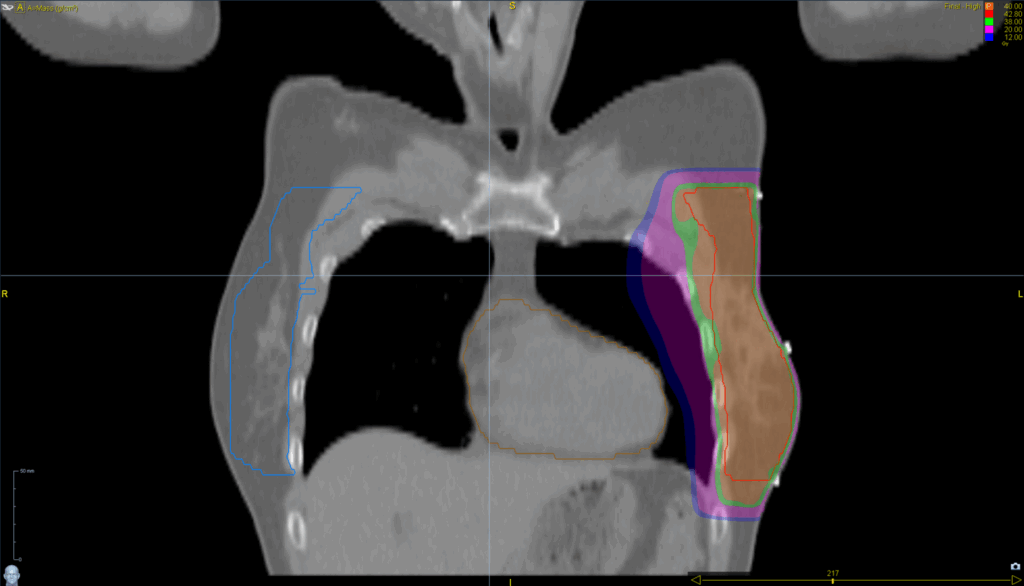

Treatment Plan Images

Fractionation / Protocol Used

40 Gy in 15 fractions

PTV(s) Volume, Length

617 cc, 18 cm

- TomoDirect™

- 4 angles

- TomoEDGE™ 5 cm